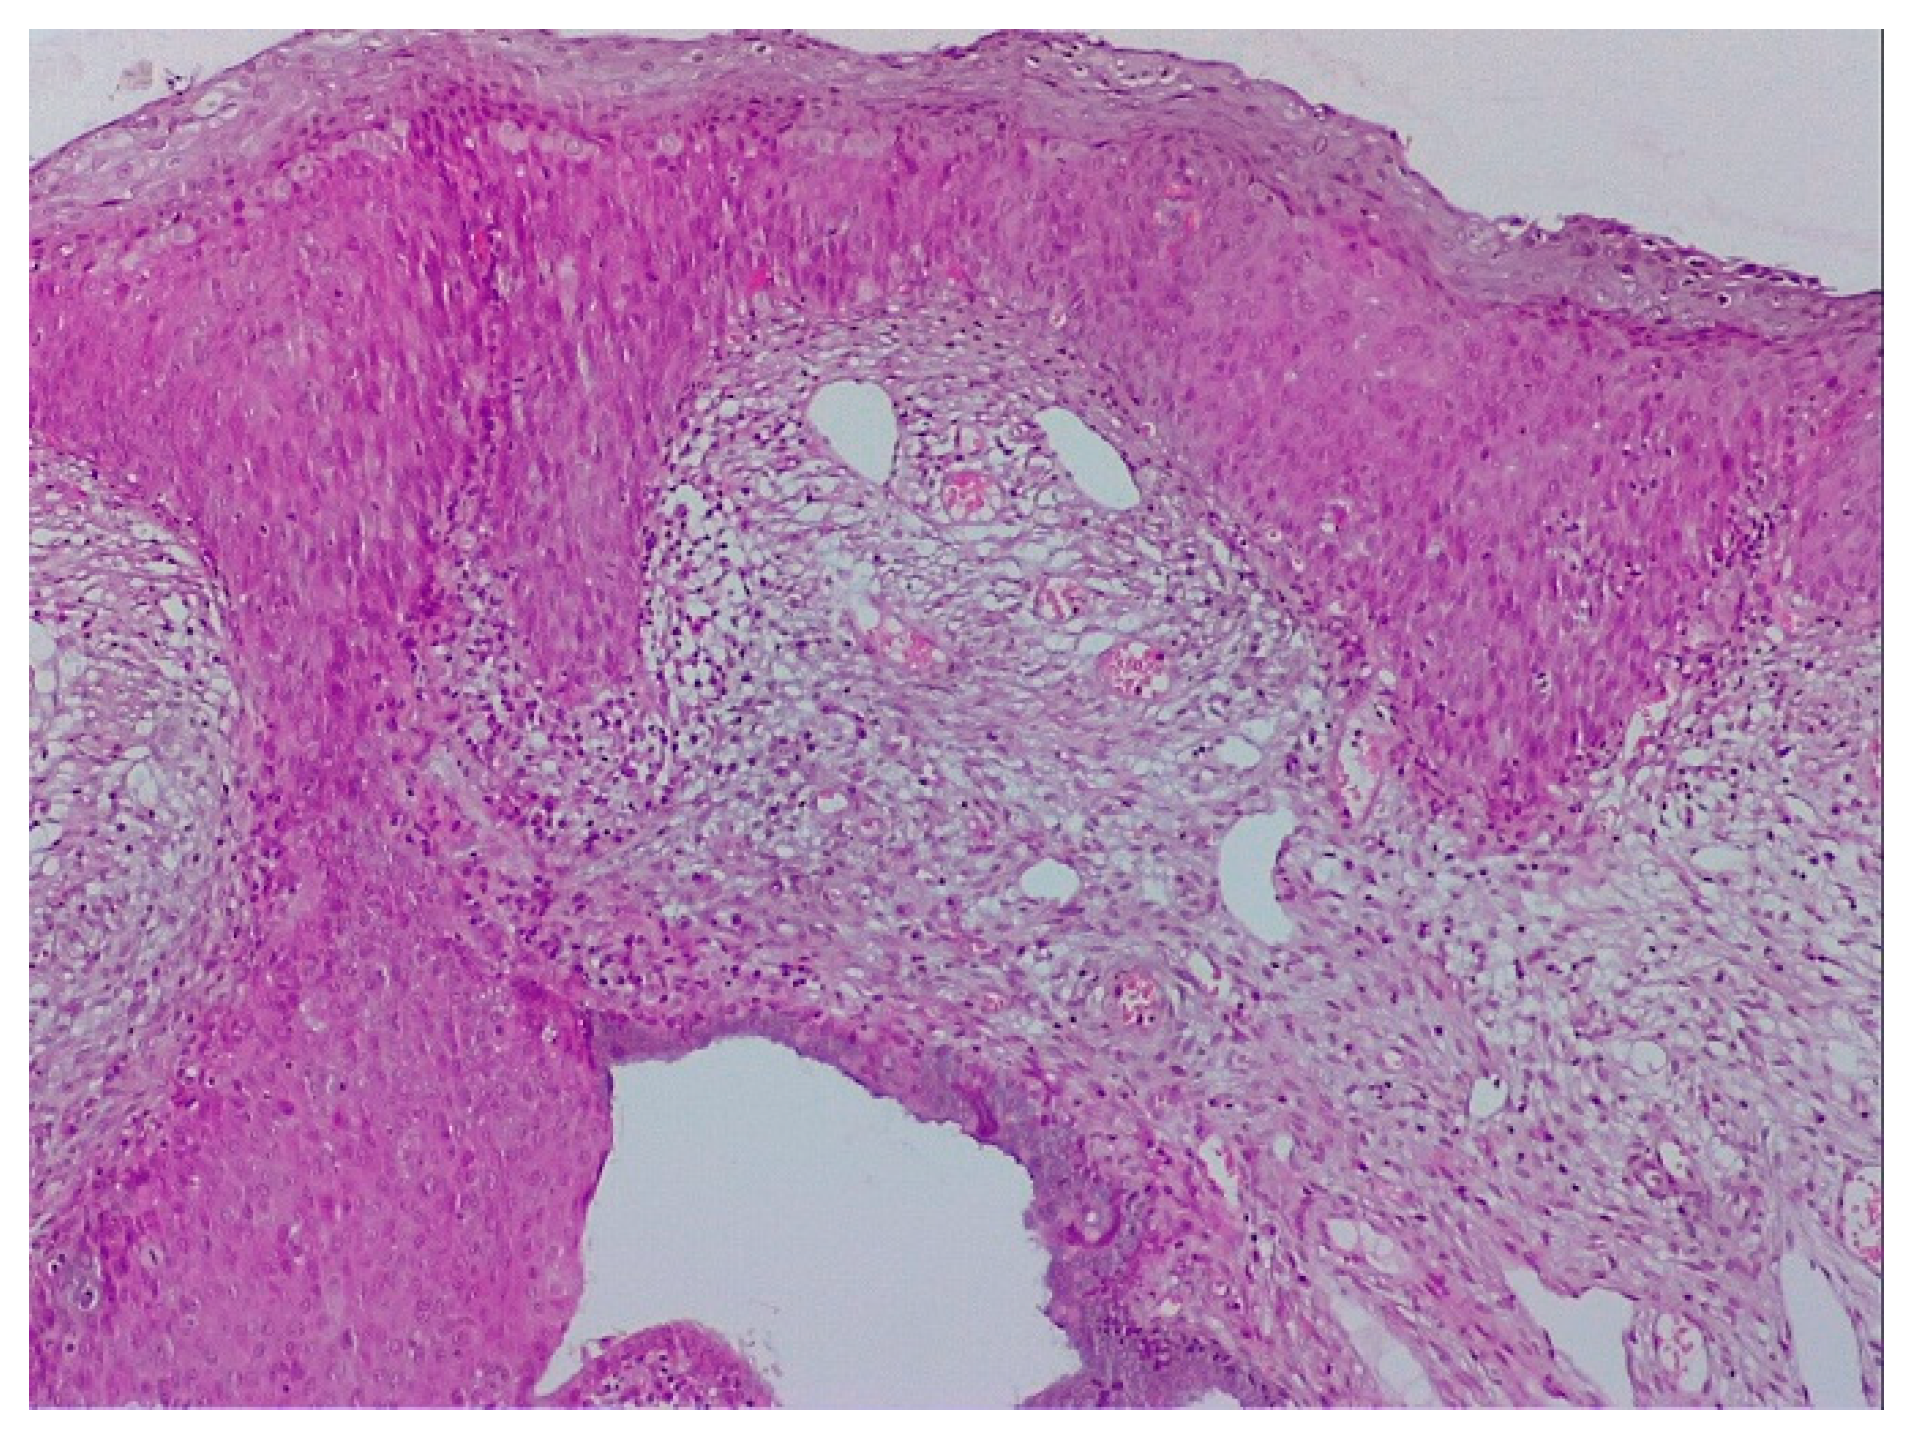

2.2. Clinical Examination